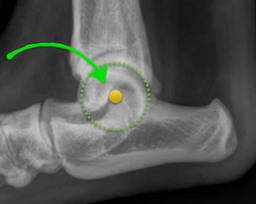

Functional Tibial line must be formed by connecting

Centre of Talus

The centre of intercondylar eminences shown in Fig. 1;

Following the identification of points of interests, and drawing of the lines of interest, i.e. the Functional Tibial Line (FTL) and the Medial Tibial Plateau Line (MTPL), another line is drawn such that the relation of new line and the FTL is 90°. Tibial plateau angle is the angle between this new line and the MTPL; this is shown in Fig. 3.